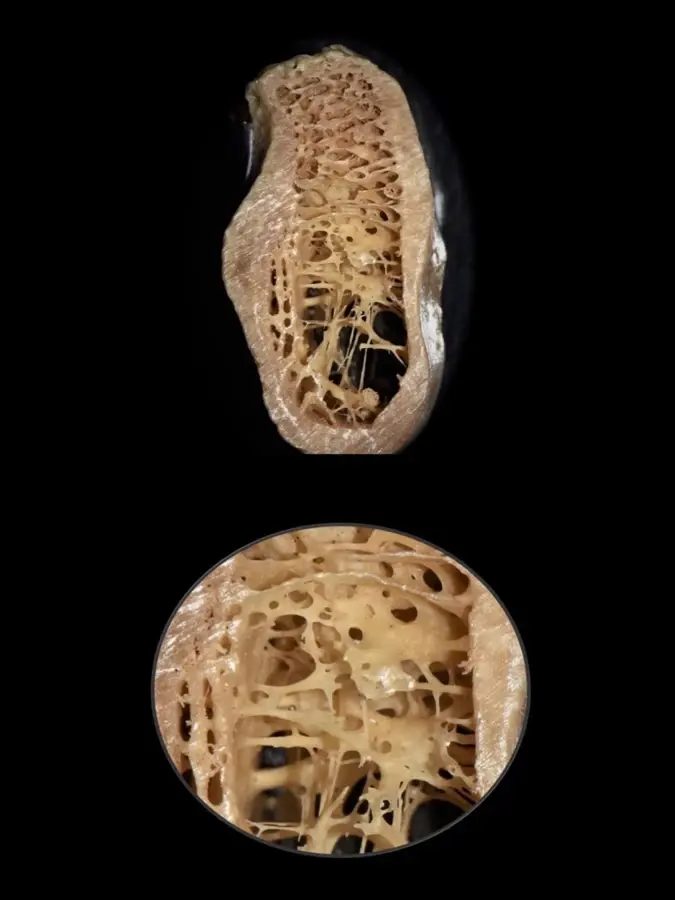

Durante años, se establecieron las propiedades biomecánicas del hueso basándose únicamente en medidas a gran escala, pudiendo diferenciarse entre el hueso trabecular y el hueso cortical. Sin embargo, actualmente es posible un mayor análisis a nivel micrométrico que permite explorar entre los componentes orgánicos, tisulares, celular y moleculares. Es así que gracias a aproximaciones nanoestructurales se muestran asociaciones entre las propiedades biomecánicas y las calidades óseas, las que se pueden presentar tanto en el hueso cortical como en el trabecular de manera indistinta. En el cortical, el espacio poroso ocupa el 5-10%, mientras que en el trabecular se encuentra en el 30-90% del total de la estructura9 (Figura 1).

Los esquemas clásicos de clasificación se basan en la proporción relativa que existe entre el hueso cortical compacto y el hueso trabecular esponjoso.10,11 El hueso tipo I se considera el menos vascular y más homogéneo, el tipo II es una combinación de hueso cortical con cavidades medulares, el tipo III está predominantemente compuesto de hueso trabecular, y el tipo IV se describe como una corteza muy delgada con trabéculas de baja densidad.12 Incluso se han propuesto diferentes analogías entre los tipos de huesos y los tipos de madera; que van desde la madera tipo balsa hasta la tipo roble.13 Posteriormente, siguieron surgiendo clasificaciones utilizando el criterio cuantitativo;14 sin embargo, su valor diagnóstico sigue siendo cuestionable.15,16

Calidad ósea según la clasificación de Lekholm y Zarb (Figura 2).

- Tipo I: hueso compacto completamente homogéneo.

- Tipo II: capa gruesa de hueso compacto rodeando al hueso trabecular denso.

- Tipo III: capa delgada de hueso compacto rodeando al hueso trabecular denso.

- Tipo IV: capa delgada de hueso compacto rodeando al hueso trabecular poco denso.